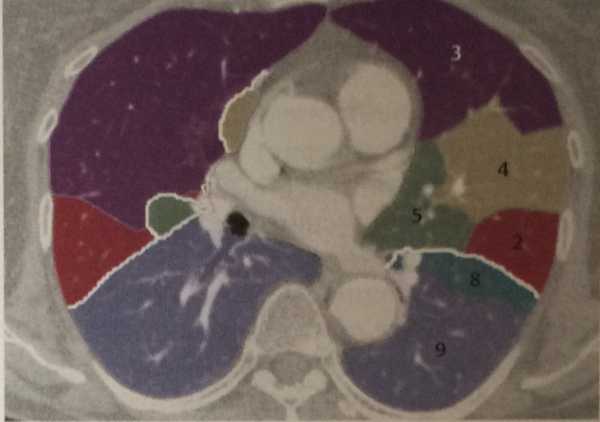

Анатомические изображения сегментов легких различных животных

Раздел: Другие животные